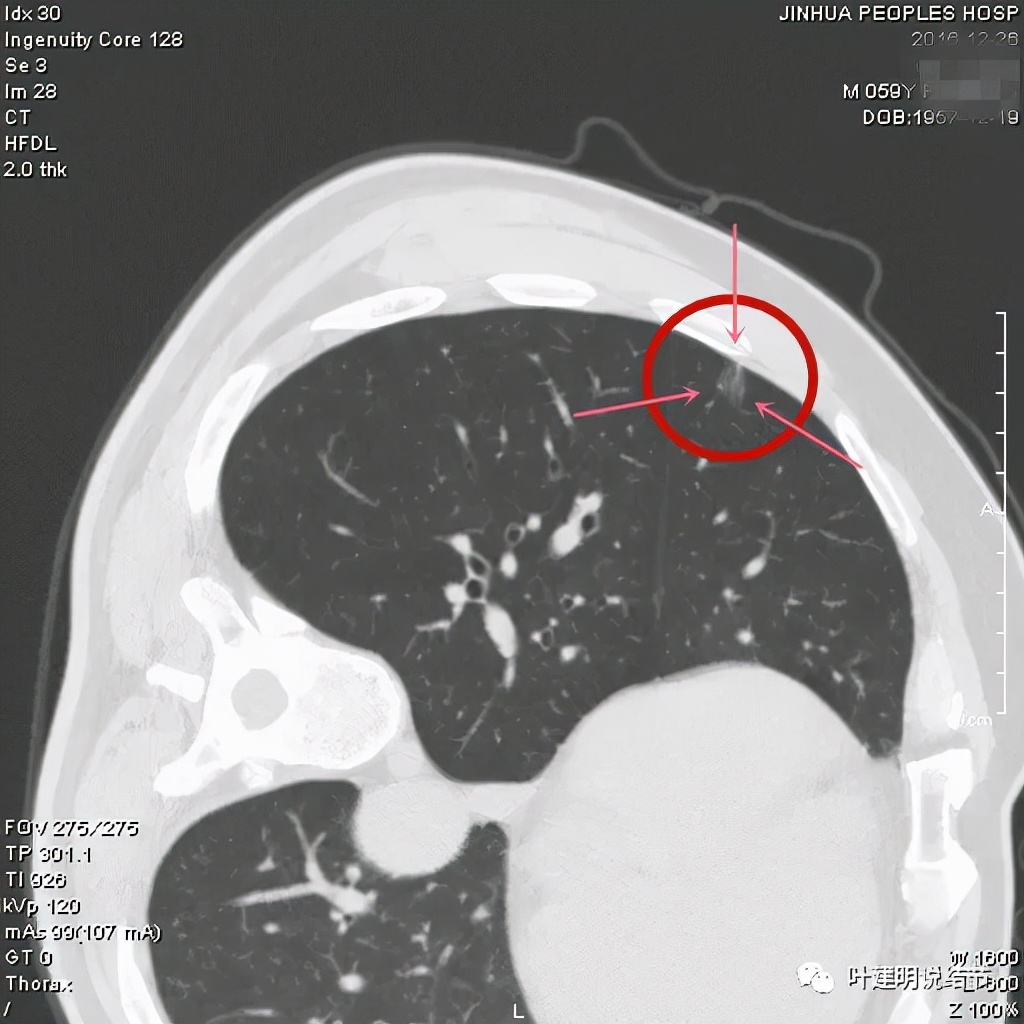

上图非常不舒服,病灶边缘有毛刺(蓝色箭头),中间有偏实性成分(粉色箭头所指),整体看密度不均杂乱

上图示明显的血管进入(桔色箭头),而且进入病灶后散大模糊,不是穿行;病灶内有高密度区域(粉色箭头)。但事后分析,绿色箭头所指的磨玻璃部分密度仍是过低,且边缘显模糊,与浸润性腺癌可能不是太符合。

以上三图均示典型的混合磨玻璃,实性成分杂乱,整体密度杂乱,并有血管征,是较为典型的浸润性腺癌影像表现。

看了后处理重建的图像,我们认为基本上应该就是浸润性腺癌了,从平扫到靶扫到靶扫描后处理,一步一步往更恶性的角度考虑。某A按我们的建议进行了单孔胸腔镜下手术,结果术中快速病理切片示:原位腺癌。我还觉得术后病理会不会升级,所以还在等石蜡切片,因为影像上,特别是后处理重建的图像太像浸润性腺癌了,结果仍是原位腺癌: